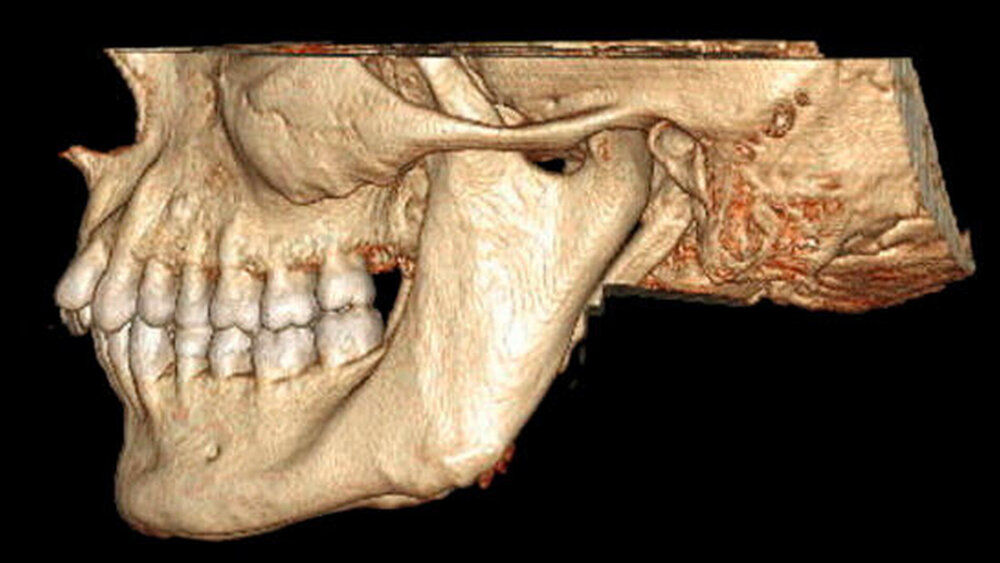

In der erweiterten radiologischen Diagnostik mittels CT zeigten sich symmetrisch angelegte Kiefergelenke beidseits ohne arthrotische Veränderungen oder signifikante Deformierungen. Ein Hinweis auf Luxation ergab sich nicht. In den axialen Schichten stellten sich beide Proc. coronoidei bis hoch in die jeweilige Fossa temporalis dar. In der 3-D-Rekonstruktion imponierten die hyperplastischen Proc. coronoidei beidseits. Diese ragten weit über die Jochbögen hinaus und schränkten dadurch die Mundöffnung ein (Abbildung 3).